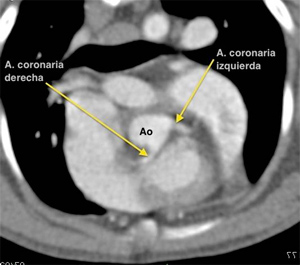

Equipo TC Siemens Somaton Scope 16 cortes con inyector de contraste

• Cuello, cavidad torácica y cavidad abdominal

• Angio-Tc: tórax y abdomen

Imágenes de la especialidad